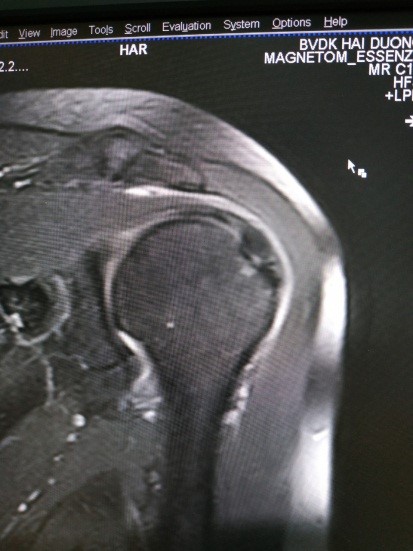

Nghiên cứu cũng chỉ ra nếu bệnh nhân không gặp một tai nạn nặng nề, nghiêm trọng thì tổn thương GCX thường thấy là rách bán phần mức độ II, trong đó hơn 90% tổn thương là rách bán phần gân cơ trên gai, chỉ có 1 trường hợp duy nhất là tổn thương phối hợp cả gân cơ trên gai và gân cơ dưới gai.

Tổn thương gân cơ dưới vai và gân cơ tròn bé cũng rất hiếm gặp. Vị trí tổn thương GCX hay gặp nhất là tổn thương rách xuyên gân (chiếm 68,8%), còn lại là rách mặt khớp và rách mặt hoạt dịch. Ngoài tổn thương thường thấy là rách bán phần GCX, các tổn thương khác đi kèm hay gặp là tràn dịch tại các vị trí ổ khớp, túi hoạt dịch dưới cơ delta, rãnh gian củ (chiếm 82,4%), tiếp đến là phù tủy xương (58,8%), ít hơn là đụng dập phù nề phần mềm (5,9%).

Hình 5. Hình ảnh rách bán phần(A), rách hoàn toàn(B)